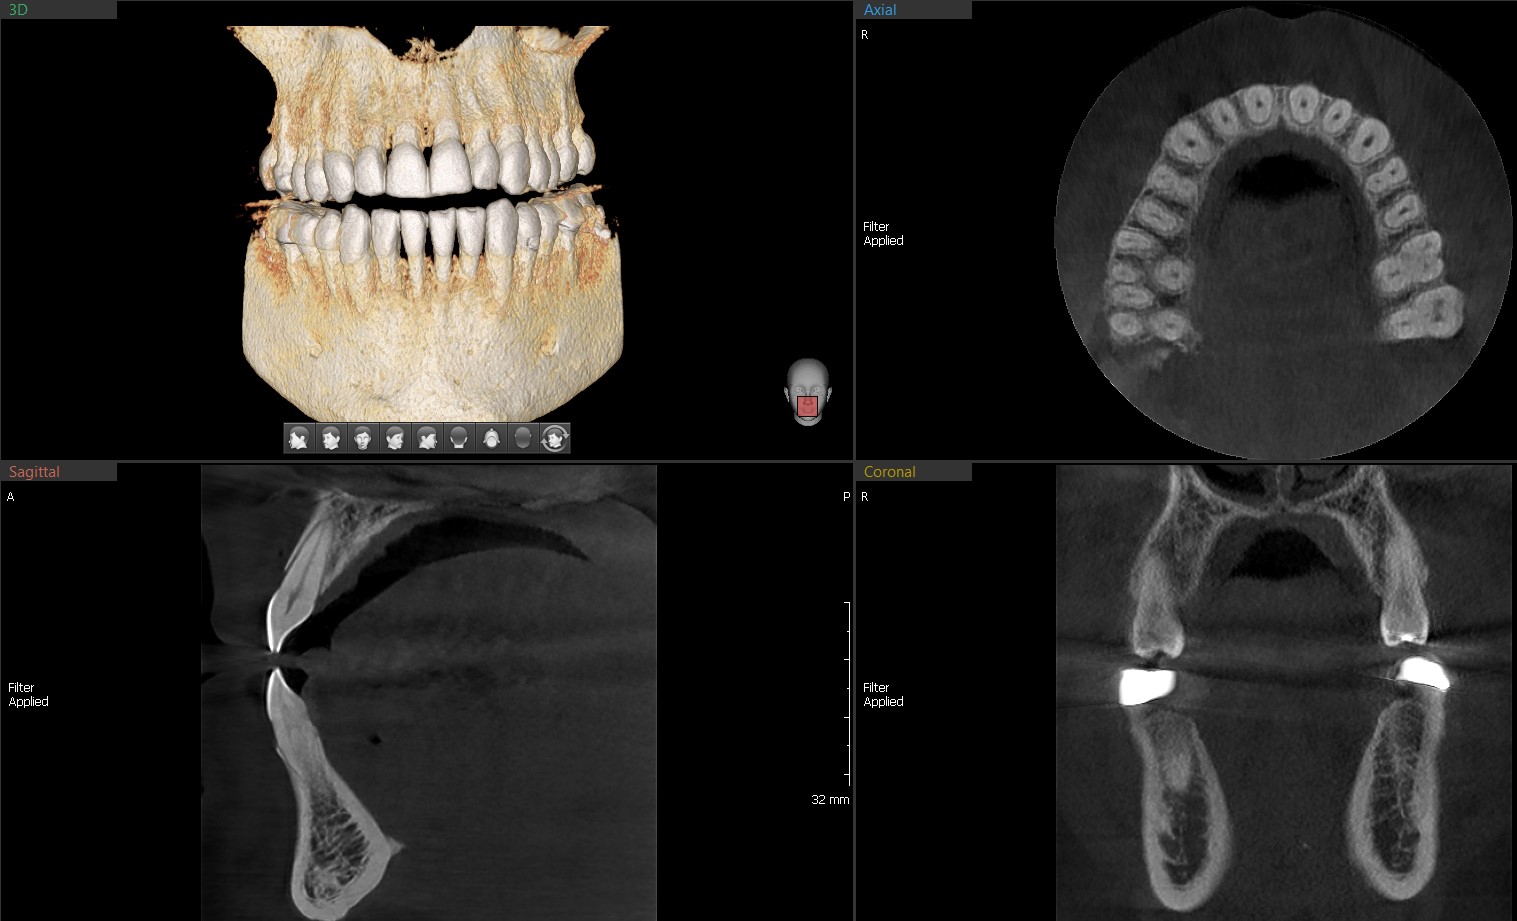

MAGIC PAN utilizes hundreds of layers of panoramic images during acquisition.

8x8 images enable fundamental diagnoses and treatment planning, including both the maxillary and mandibular areas, in a single scan. It is useful for implant surgeries and diagnoses.

The next step in cephalometric technology, Vatech's new Rapid Ceph minimizes motion artifacts and enables faster diagnostic workflow while providing the high-quality digital images.